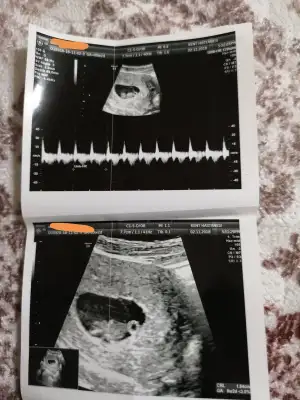

Benim icin sadece saglikli olmasi onemli cinsiyetini merak etmiyorum hic kuzum ama atarim neden olmasin8. Hafta da ultrsn atarsın tahmın atarım![]()

8. Hafta da ultrsn atarsın tahmın atarım![]()